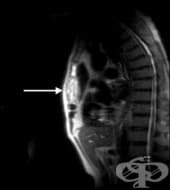

ЯМР на китка

ЯМР на китка е неинвазивен метод от образната диагностика, при който с помощта на магнитно поле и ра...